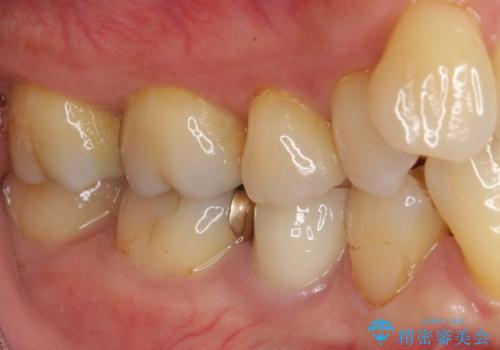

- 食べ物の繊維が引っかかるとのことで来院された患者様です。

ご自身の歯質と金属の詰め物(ゴールドインレー)との間に、わずかに隙間ができていました。

ゴールドインレーは非常に適合性が良いものなので、再度ゴールドインレーによる治療を提案させていただいたのですが

患者様より「下の歯だから目立つのでセラミックがいい」とのご希望だったので、セラミックインレーにて治療をすることとなりました。

拡大鏡視野下で、ゴールドインレー、虫歯の除去を行い、セラミックインレーに適した形に整えました。

特に異常もなく見た目、噛み合わせともに満足していただけました。